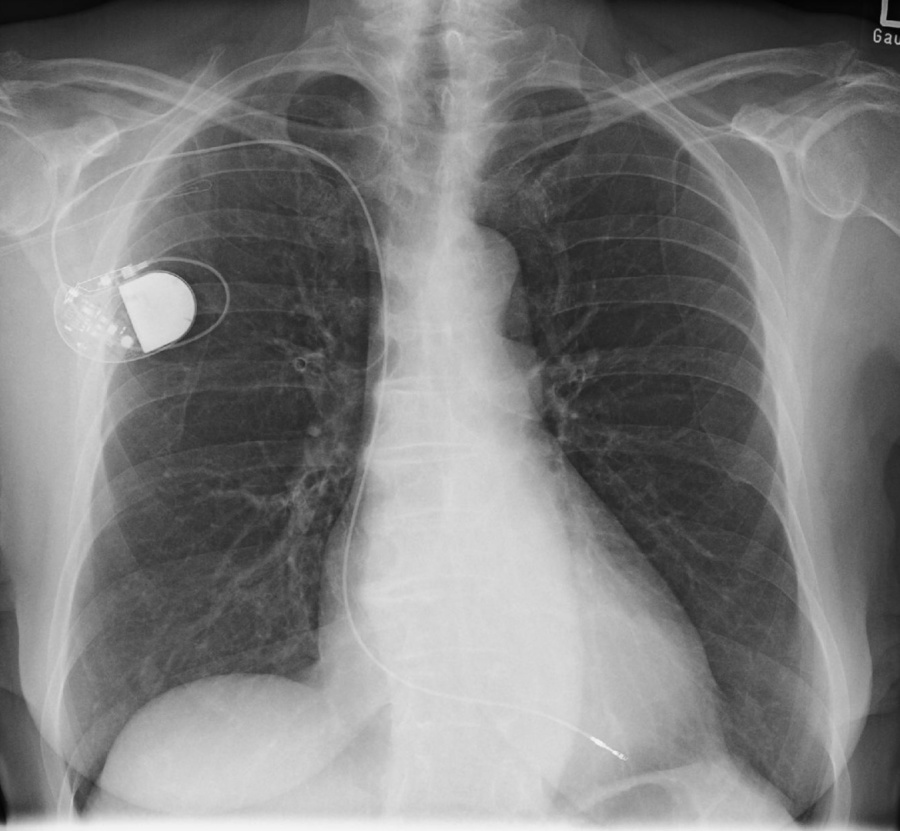

Schrittmacher- Defibrillatorkontrollen

Implantierte Herzschrittmacher und Defibrillatoren müssen regelmäßig auf ihre Funktionsfähigkeit untersucht werden. In der Abfrage von extern werden der Batteriestatus und die elektrische Leitungs- und Stimulationsfähigkeit der Elektroden untersucht und die Programmierung bei Bedarf angepasst.